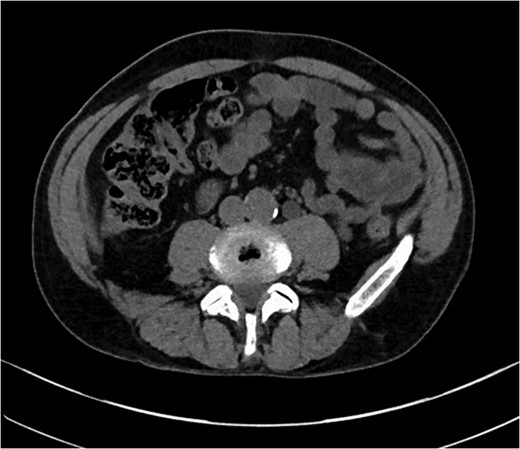

A previously fit and well 68-year-old male presented with a 6-month history of pain in the right hip. On examination this was localised to the superior area of the hip joint where a bony mass could be palpated. A pelvic radiograph was performed (Fig. 1) showing a bony exostosis on the right iliac wing. To characterise the lesion further, a pelvic Magnetic resonance imaging (MRI) scan was performed (Fig. 2). Appearances were consistent with an osteosarcoma and referral to the local sarcoma centre for histological investigation was made. Surprisingly, sampling from biopsy showed invasive well-differentiated adenocarcinoma. Staging computed tomography (CT) scanning did not reveal a primary source for the tumour but did identify thickening of the descending colon (Fig. 3) and lymphadenopathy involving the left supraclavicular, thoracic, paravertebral, retro-crurual and right inguinal regions. There was no evidence of tumour in the liver, lung or other parts of the skeleton. Subsequently, colonoscopy identified the thickened lesion as a hepatic flexure adenocarcinoma (Fig. 4). Biopsy at the time of endoscopy revealed the lesion at the hip to be a metastasis.

CT abdomen demonstrating thickened segment of ascending colon.